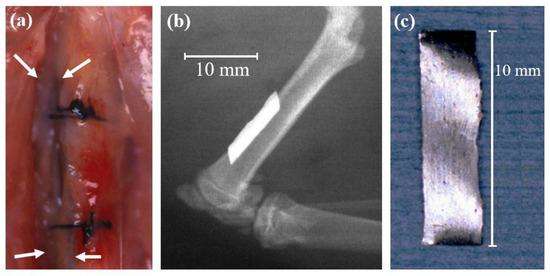

- Imai, K.; Hiromoto, S. In vivo evaluation of bulk metallic glasses for osteosynthesis devices. Materials 2016, 9, 676. [Google Scholar] [CrossRef] [PubMed]

- Imai, K. In vivo investigation of Zr-based bulk metallic glasses sub-periosteally implanted on the bone surface. J. Mater. Sci. Chem. Eng. 2016, 4, 46–51. [Google Scholar] [CrossRef]

- Kokubun, R.; Wang, W.; Zhu, S.; Xie, G.; Ichinose, S.; Itoh, S.; Takakuda, K. In vivo evaluation of a Ti-based bulk metallic glass alloy bar. Bio-Med. Mater. Eng. 2015, 26, 9–17. [Google Scholar] [CrossRef]